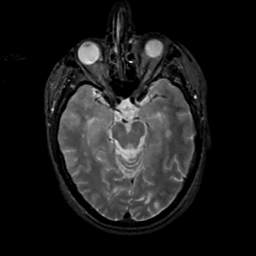

MR Study #14, June 2, 1991 -- Slice #19